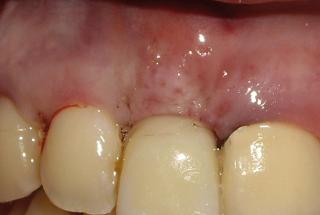

Clinical cases

MPI closely monitors clinical cases in the market to ensure their correct functioning and successful outcome.